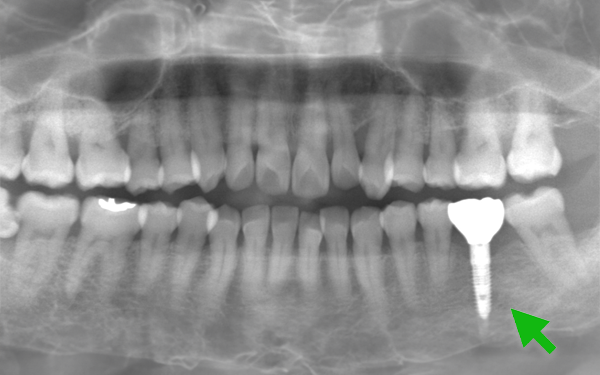

Case13.

| 主 訴 | 歯がない部分を治療したい |

|---|---|

| 治療期間 | 約4ヶ月 |

| 治療費 | 913,000円(税込) |

| 治療内容 | 下の歯の欠損をインプラント、 上の歯の欠損を入れ歯で治療しました。 治療期間は4ヶ月、通院回数は6回ほどです。 |

| 治療のリスク | インプラントの手術の後は腫れ、 痛みが出ることがあります。 入れ歯は稀に欠ける事があります。 |